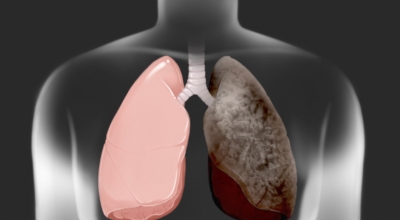

폐에 발생된 악성 종양을 말하며 오랜 기간 흡연해온 남성들에서 발병률이 높고 최근에는 각종 환경적인 요인의 영향과 간접흡연으로 흡연하지 않는 여성에서도 많이 발생하고 있습니다. 증상을 느껴 병원을 찾았을 때는 수술하기 늦은 경우가 많아 사망률이 매우 높은 암입니다. 폐 자체에서 발생하거나 다른 장기에서 발생된 암이 폐로 전이되어 발생하기도 하고 특별한 초기 증상이 없는 경우가 많고 암이 진행된 후에도 동일한 감기 증상인 기침과 가래 외의 특이 증상이 나타나지않아 증상만으로는 진단이 쉽지 않습니다.